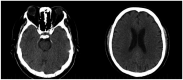

Background: Hashimoto's encephalopathy (HE) is a controversial immunological neuropsychiatric disease, with a poorly understood pathogenesis. It is characterized by symptoms of acute or subacute encephalopathy which usually occur in the presence of elevated levels of antithyroid antibodies. Even though it is also known as steroid responsive encephalopathy associated with autoimmune thyroiditis (SREAT), some cases appear to be steroid-resistant. This review examined whether treatment of Hashimoto's encephalopathy with intravenous immunoglobulin (IVIG) is associated with better clinical outcomes than the standard therapy. Additionally, we presented a case of a 59-year-old man who presented with severe neurological manifestations and was successfully treated with intravenous immunoglobulin.